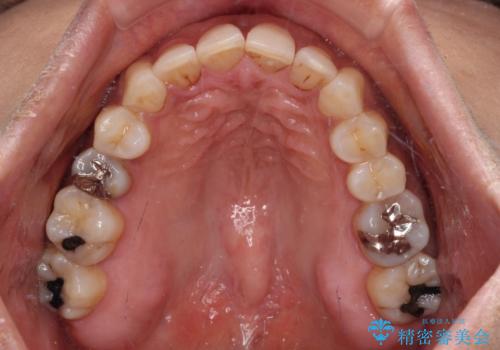

- 上下前歯のデコボコ改善をインビザラインにて行いたいとのことで来院された患者様です。

インビザラインをご希望のことで、IPR(歯と歯の間を削る)などによりスペースを獲得して、排列していくこととしました。

骨格的に上下顎が左右にずれていたため、正中位置は現状を維持したまま歯列不正を解消していくことになります。